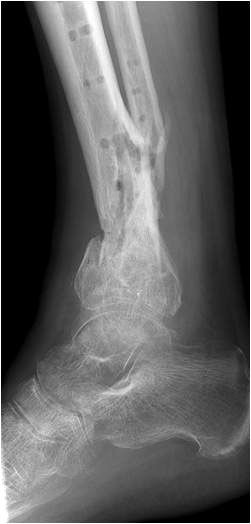

• Primäre oder posttraumatische Arthrose des OSG und USG (Abbildung 1, Abbildung 2).

• Revision einer gescheiterten Fusion des OSG/ USG (Abbildung 3, Abbildung 4).